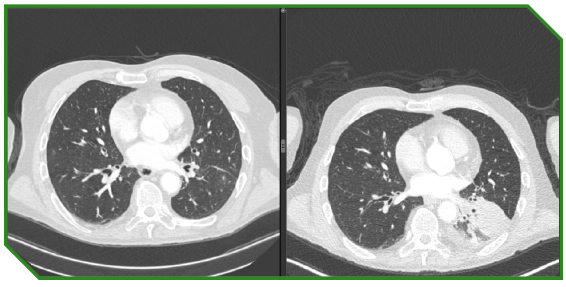

Paciente masculino de 78 anos com carcinoma espinocelular de laringe, tratado inicialmente com abordagem definitiva local, evoluindo posteriormente com recidiva local e progressão metastática pulmonar. Ao longo do curso da doença, foi submetido a múltiplas linhas terapêuticas, incluindo cirurgia, radioquimioterapia, quimioterapia sistêmica e imunoterapia isolada e em combinação, refletindo a complexidade do manejo longitudinal do R/M HNSCC.